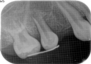

当時の歯の移植は、移植歯を抜歯したら、歯の根の表面の徹底的な清掃(掻爬)と、根管治療を口腔外で行いその歯を移植していました。しかし、それでは移植歯は移植された所の歯槽骨(もともとの歯を支える骨)とどんなに上手くいっても骨性癒着を起こします。この癒着した歯の根は時間と共に周囲の骨組織に吸収され、やがて歯の根はあとかたも無くレントゲンから消え去り、まるで乳歯が抜けるように根の無くなった歯が抜けていきます。これが5年もてば成功といわれた所以です。

現在は、ドナーとなる歯の抜歯前に移植される側の処置を終了し、ドナーの歯を抜歯するとほぼ同時に、当院では3秒以内に受容側の中にドナーの歯を入れます。これはとても速いスピードであるといえ、このスピードで確実に行う為に、いろいろな研究を行い、CTスキャンのデータを応用した現在の移植のシステムを構築致しました。

このようにして移植された歯は、歯の根の表面にある歯根膜と言う組織がほぼ完全に保存され、生着(生きた状態で移植されて機能する事)する事によって、将来矯正治療で歯を移動する事もできますし、被せもの等を行えば全く移植歯である事は気が付かれないレベルで仕上がります。